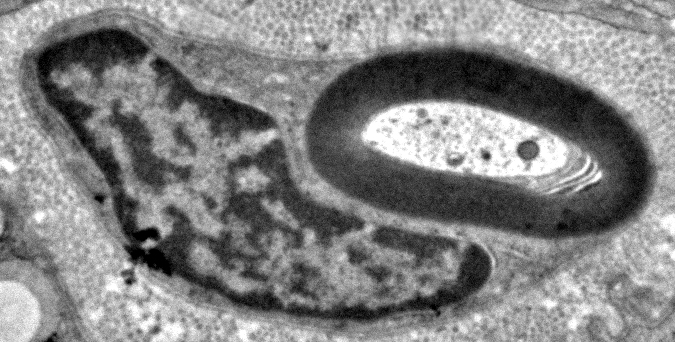

Myelin Pathology: Early

From: R Schmidt